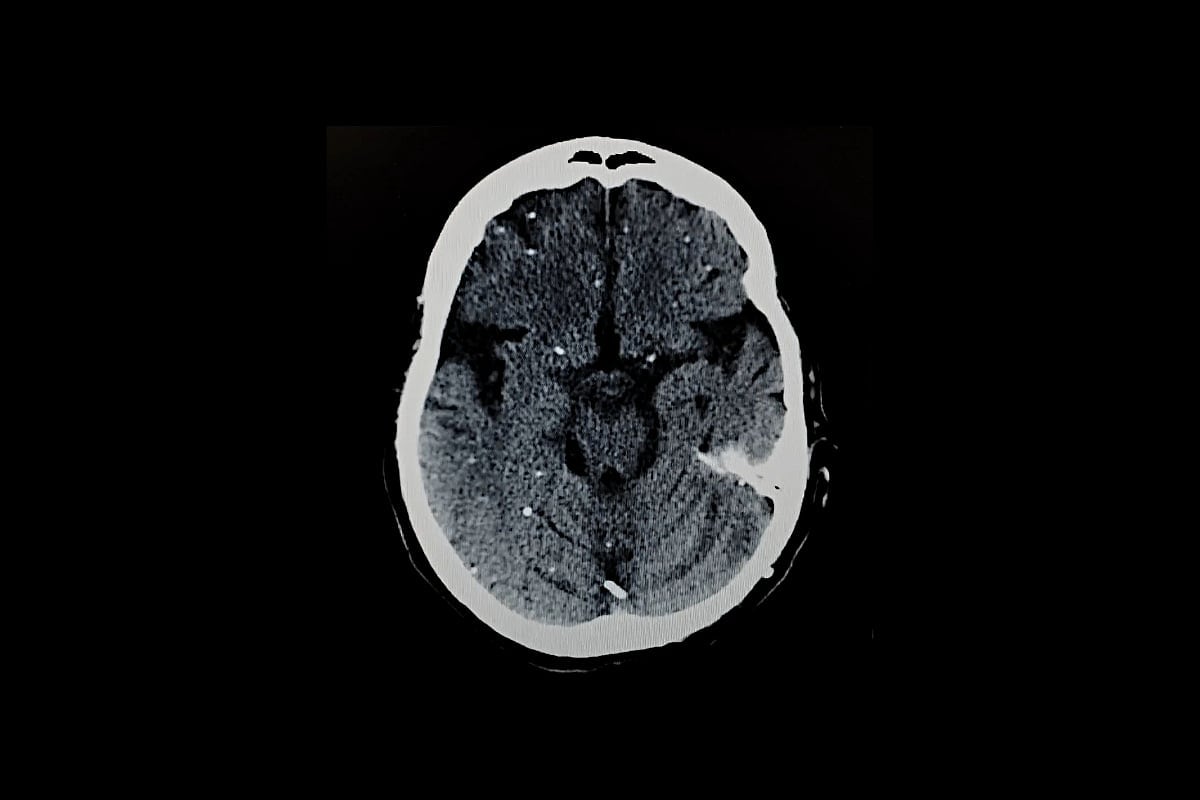

Se protege formando pequeños quistes, principalmente en el cerebro y los músculos. Cada quiste puede albergar cientos de parásitos latentes.

Estos parásitos pueden despertar más tarde, especialmente en personas con sistemas inmunitarios débiles, lo que a veces puede provocar graves problemas cerebrales o oculares. La infección durante el embarazo también puede dañar al feto en desarrollo.

Estos quistes se encuentran con mayor frecuencia en neuronas, células que conforman el sistema nervioso. Pero también aparecen en el corazón y el músculo esquelético, lo que ayuda a explicar por qué las personas pueden infectarse al comer carne poco cocinada.

Estos pueden propagarse por el cuerpo y causar enfermedades graves como daño cerebral (encefalitis toxoplásmica) o pérdida de visión (toxoplasmosis retiniana).